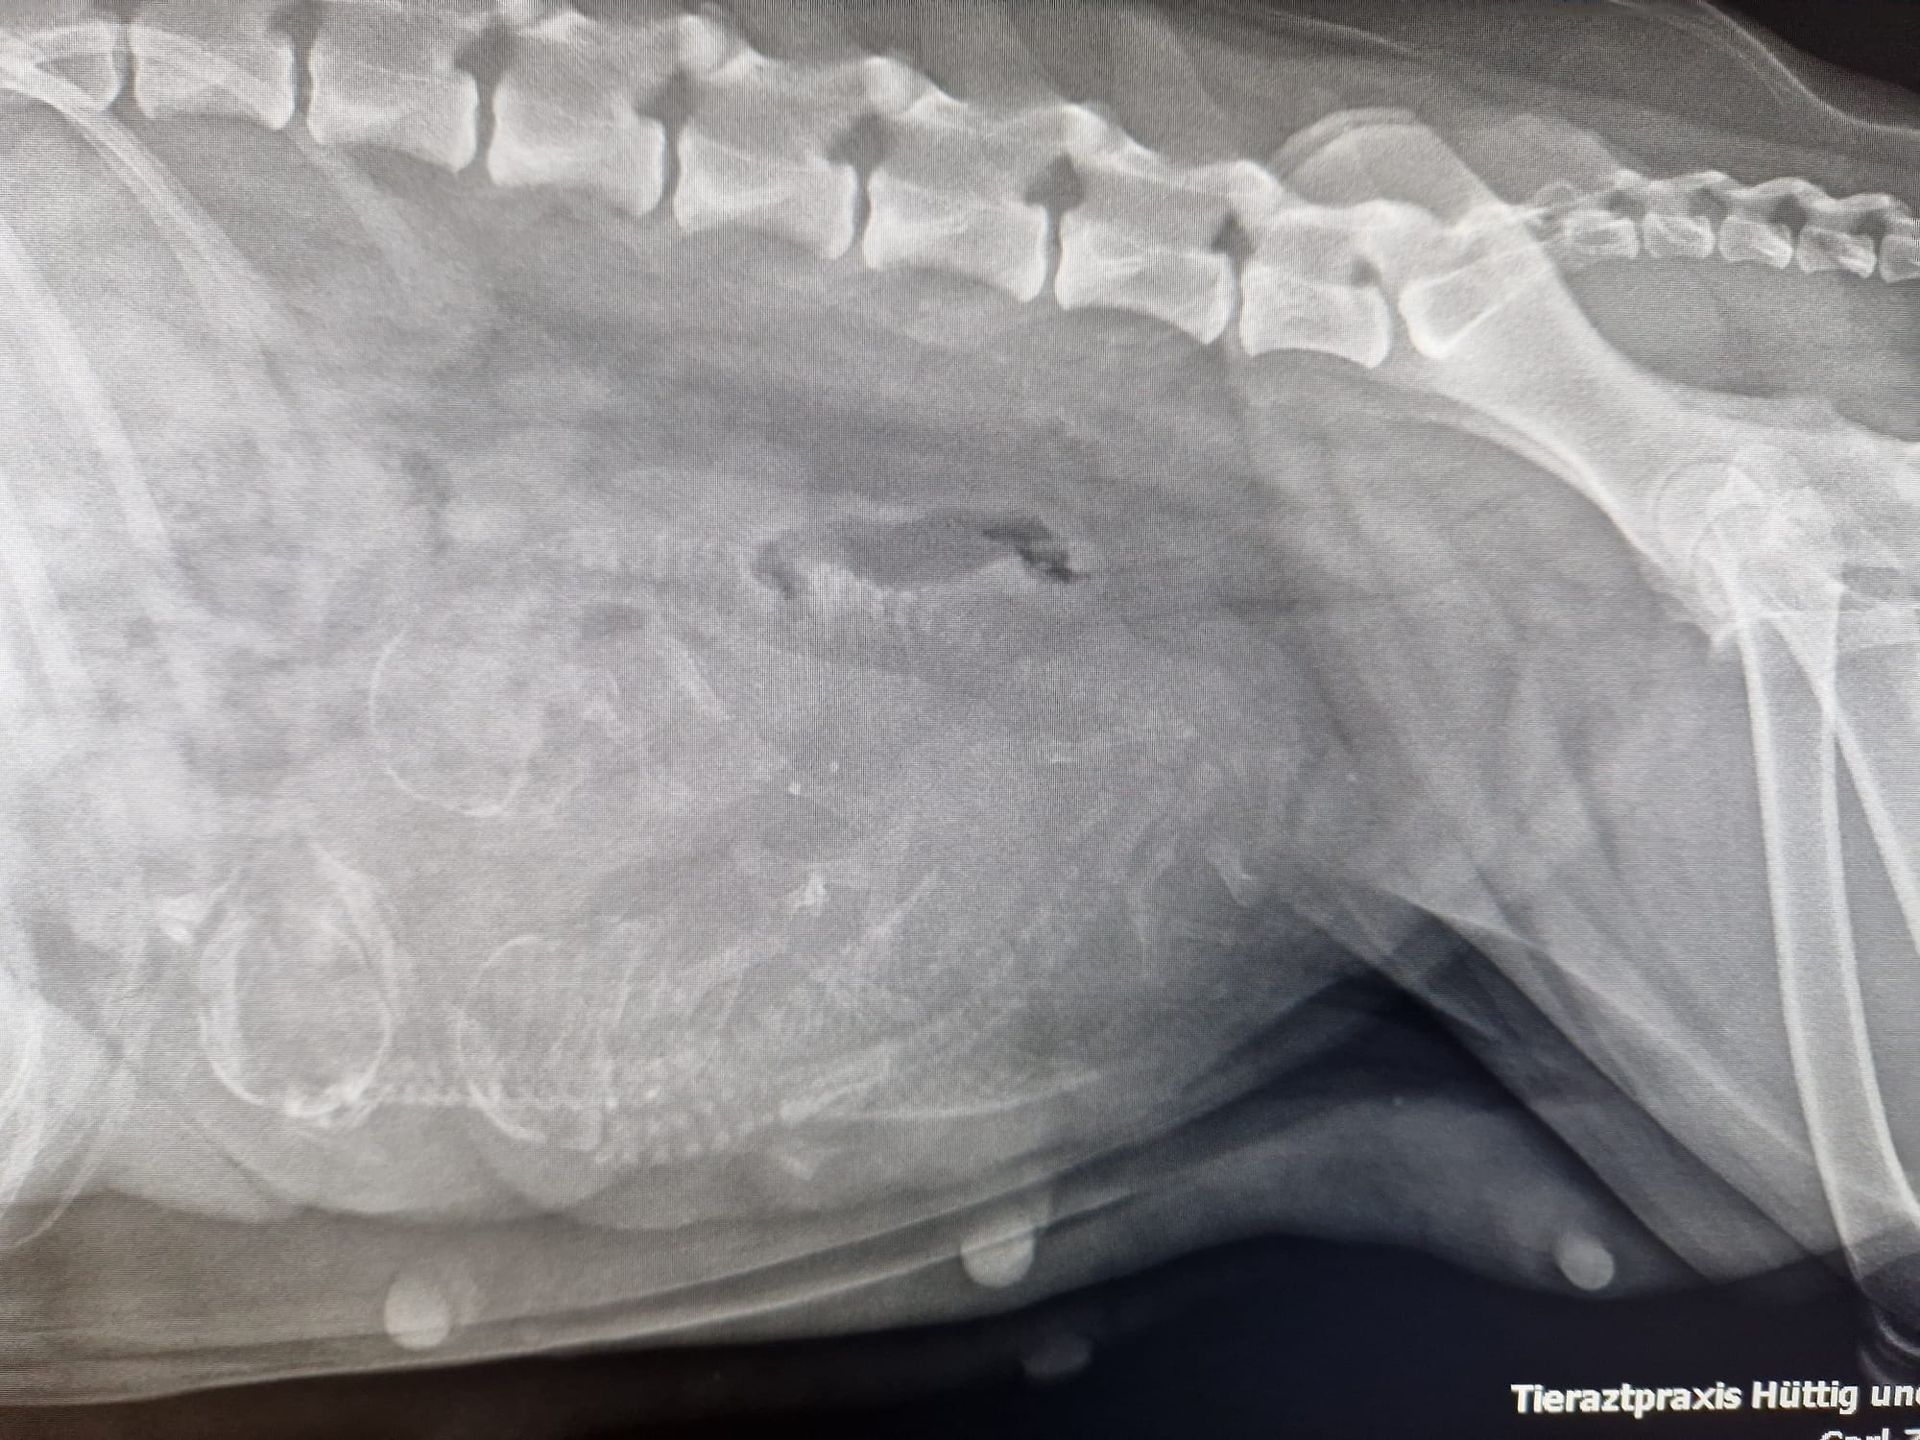

Livi ist eine instinktsichere, entspannte Mama und kümmert sich voller Hingabe um ihre Brut. Nach einer sehr langen Eröffnungsphase hatte letztendlich nur der Wehentropf beim Tierarzt die Geburt einleiten können. Trotz langer Pausen konnten alle Welpen auf natürlichen Weg geboren werden und wir genießen die kleine Familie.